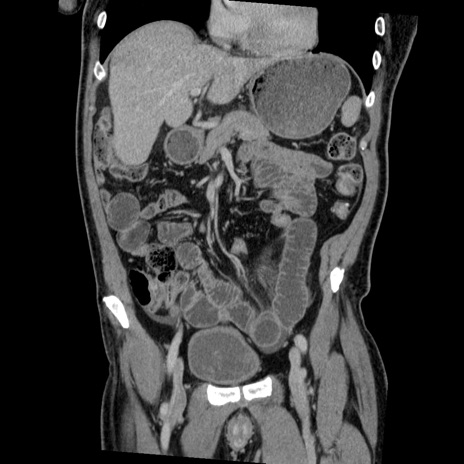

症例22(冠状断像)

【症例】50歳代男性

【主訴】腹痛

【現病歴】AVMからの被殻出血のため回復期リハ病棟入院中。 本日午後3時頃急に下腹部痛が出現した。

【既往歴】AVM、被殻出血、虫垂炎、高血圧

【身体所見】意識晴明、左半身不全麻痺、会話の理解は良好、36.5°C、腹部:膨隆、全体に板状硬、下腹部正中に圧痛点あり、反跳痛-、筋性防御不明、右下腹部にope scar

【データ】WBC 9400、CRP 0.06